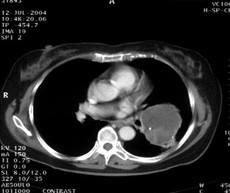

女,62歲。右大腿滑膜肉瘤,術(shù)后左下肺轉(zhuǎn)移,9.5×7.5cm。CT引導(dǎo)下瘤內(nèi)注射今又生,1×1012VP/次/周,共8次,結(jié)合60Gy放射照射。治療后腫瘤縮小48%,CT示瘤內(nèi)低密度區(qū)占50%以上,即腫瘤大部分壞死。

治療前

治療后